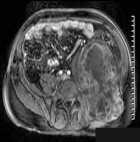

K.M. - 42 year old male c/o a sharp, moderate, constant pain in his lower back radiating down his LLE for four months. He reports some LLE weakness, which does not limit his ambulation. He has also noticed a bulge around his left pelvis. No F/C.

Zoom image: Radiological image Radiological image.